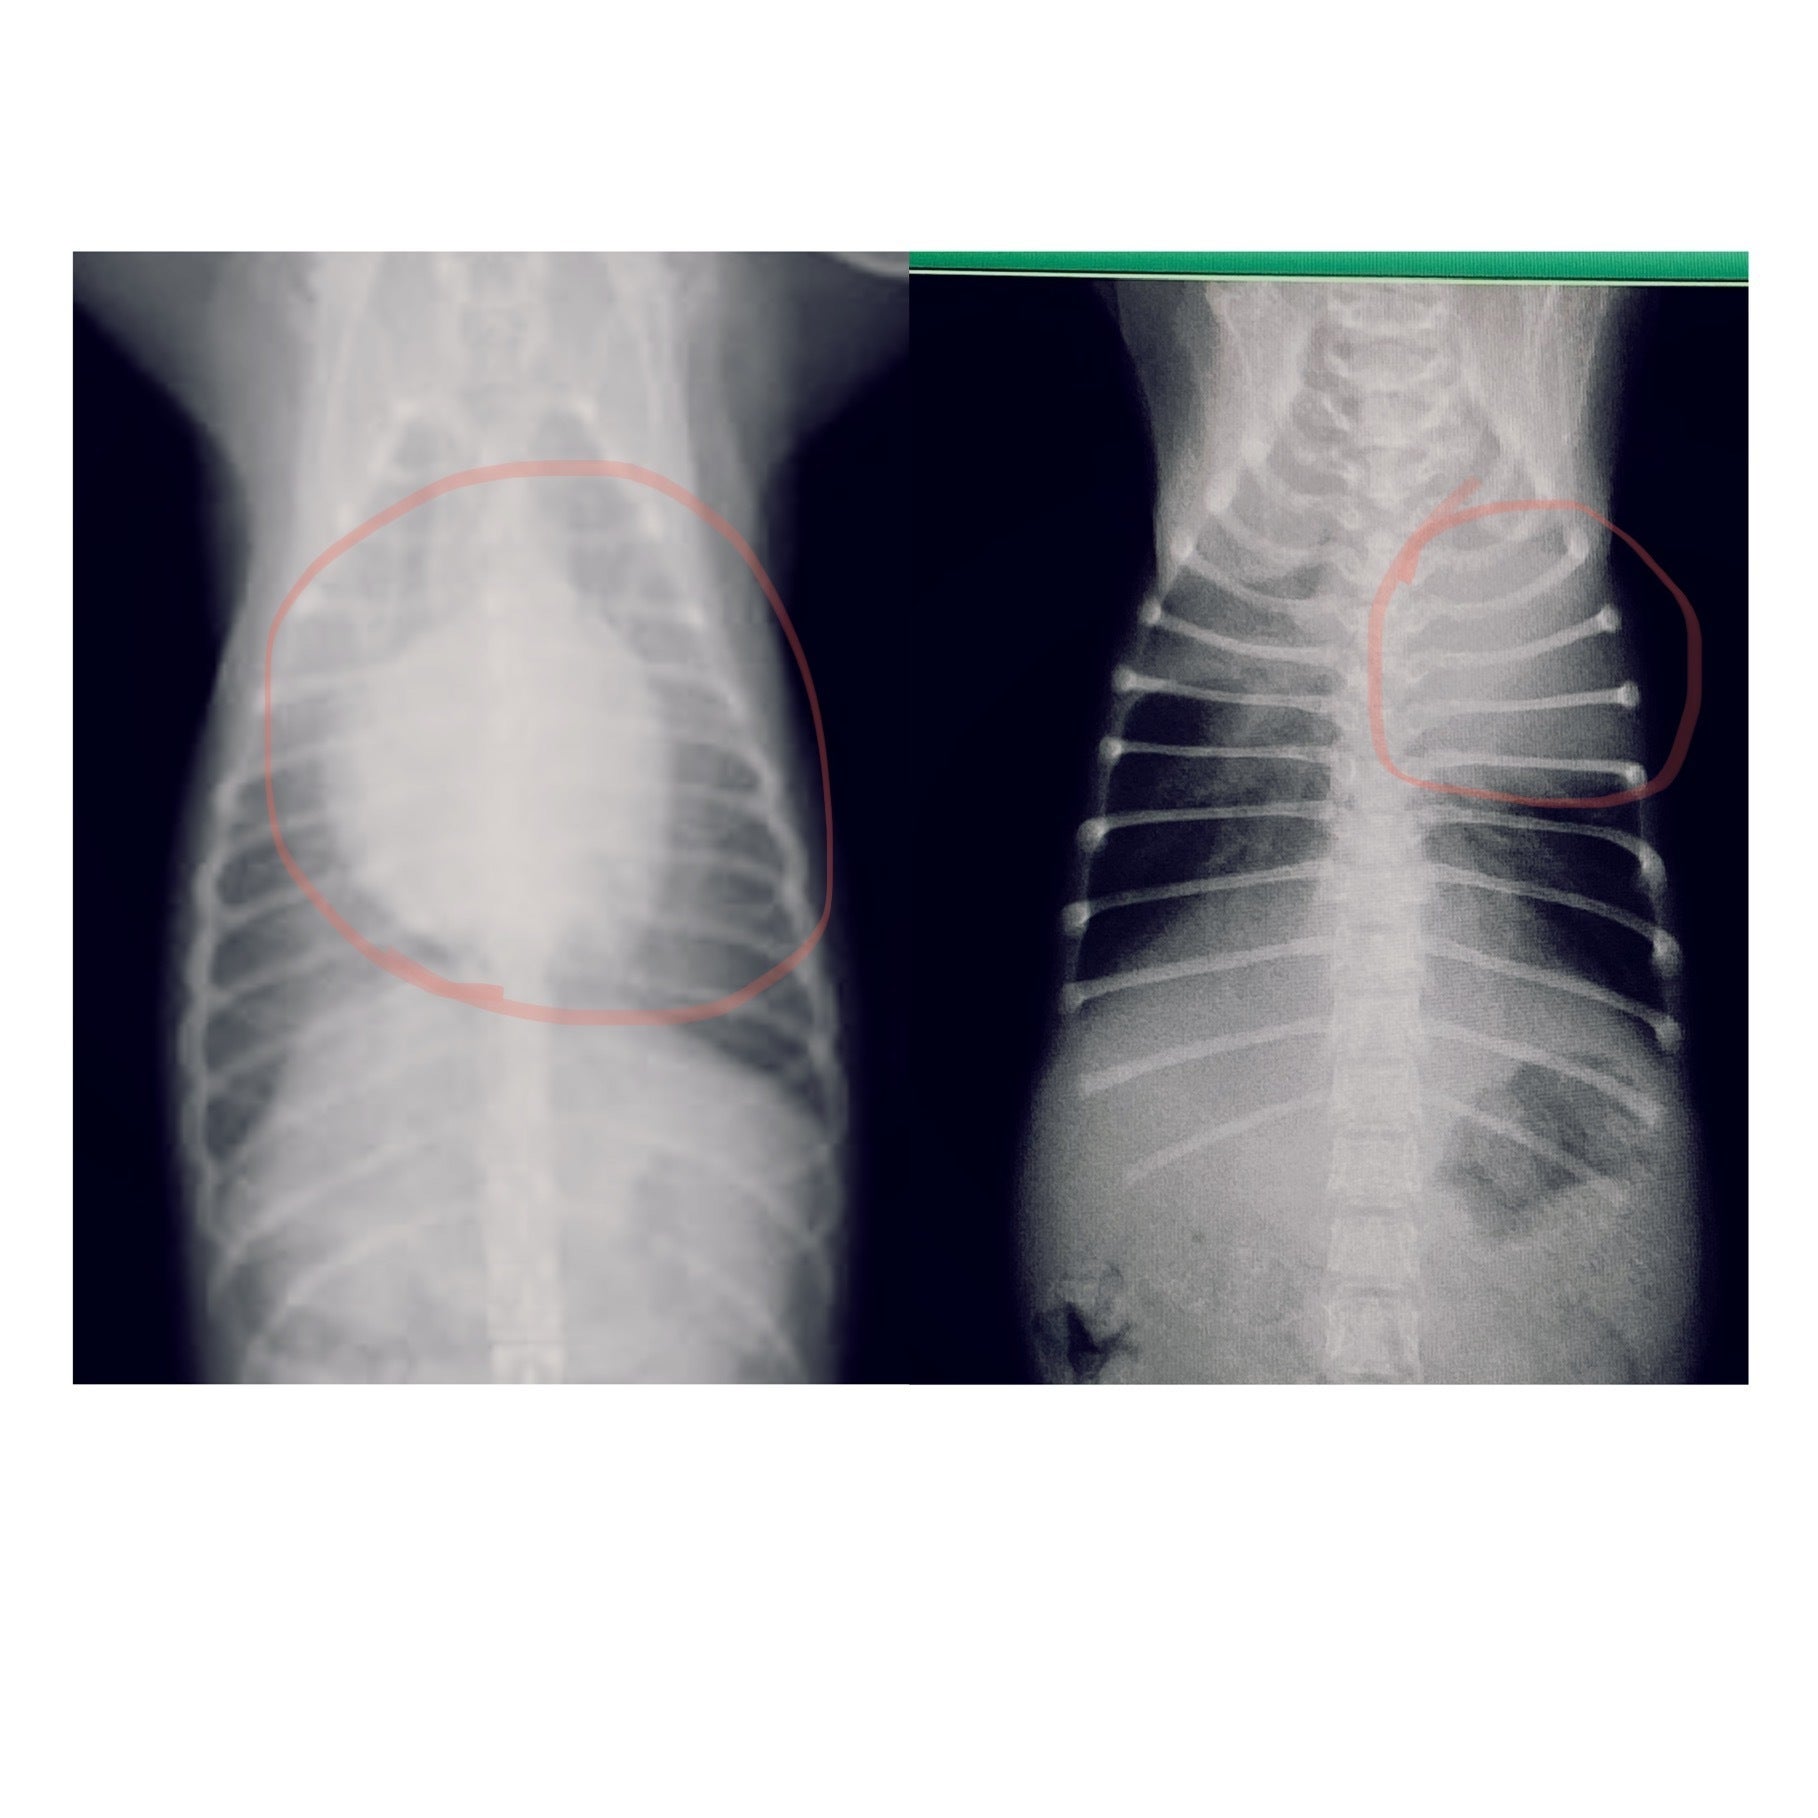

左が通常の子のレントゲン、右がうどんちゃんのレントゲンです。

赤丸の中心が心臓ですが、通常と大きさと位置が大きくズレていることが分かると思います。

肋骨も庇うためか歪んでしまっていました。。

肺も小さいので肺活量がかなり少なく、すぐにバテて動けなくなります…